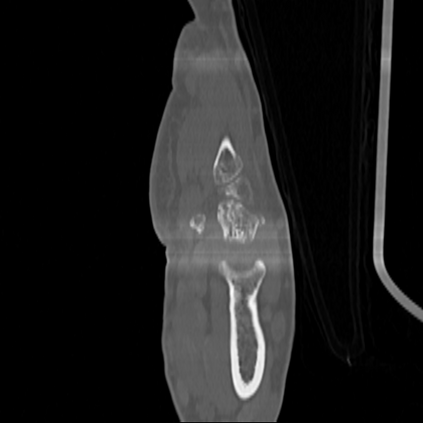

CT reconstruction provides radiologists with images for diagnosis and treatment, yet current deep learning methods are typically limited to specific anatomies and datasets, hindering generalization ability to unseen anatomies and lesions. To address this, we introduce the Multi-Organ medical image REconstruction (MORE) dataset, comprising CT scans across 9 diverse anatomies with 15 lesion types. This dataset serves two key purposes: (1) enabling robust training of deep learning models on extensive, heterogeneous data, and (2) facilitating rigorous evaluation of model generalization for CT reconstruction. We further establish a strong baseline solution that outperforms prior approaches under these challenging conditions. Our results demonstrate that: (1) a comprehensive dataset helps improve the generalization capability of models, and (2) optimization-based methods offer enhanced robustness for unseen anatomies. The MORE dataset is freely accessible under CC-BY-NC 4.0 at our project page https://more-med.github.io/